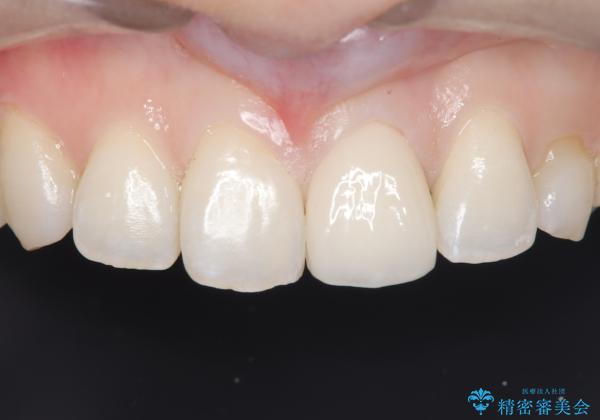

【変色歯】コンポジットレジンからセラミックへ

- 以前に前歯を折れた時、コンポジットレジンで修復したが、変色してきたことを主訴に来院されました。

今回は、セラミッククラウンによる修復を希望され、治療を行っています。

コンポジットレジンは、経年変化しやすい材料ですが、セラミックは変色しずらい材料となります。